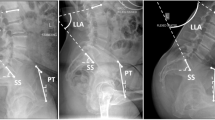

In addition to routine preoperative pelvic and hip radiographs, we took three lateral spinopelvic radiographs for each patient in standing, sitting, and LD positions in our preoperative protocol. For the standing position, the patient stood upright with the side perpendicular to the X-ray detector, arms crossed in front, feet shoulder-width apart, and head in a neutral forward-facing position (Fig. 1). For the sitting position, the patient sat upright on a radiolucent chair with the side perpendicular to the X-ray detector, arms across the chest, feet flat on the floor, hips/knees at 90° angles, and head in a neutral forward-facing position (Fig. 2). For the LD position, the patient lay on their side perpendicular to the X-ray detector, with the operative side above and positioned at 30° of hip and knee flexion, and the lower leg positioned at neutral hip and 45° of knee flexion. The pelvis was fixed so that both anterior superior iliac spines aligned vertically against the table (Fig. 3). In all three positions, the central ray was directed at the level of the iliac crest (L4-L5).

We measured the following SPPs in all three radiographs (Figs. 1, 2 and 3). Sacral slope (SS) was measured by the angle between a line along the S1 superior endplate and a horizontal line. Pelvic Tilt (PT) was measured by the angle between a line from the center of the femoral head to the midpoint of S1 superior endplate and a vertical line. Pelvic Incidence (PI) was measured using the angle between a line perpendicular to the midpoint of S1 superior endplate and a line connecting this point to the center of the femoral head. If the centers of both femoral heads did not overlap, we used the midpoint of the line connecting both femoral head centers. Ante-inclination (AI) was assessed by measuring the angle between a line connecting both ends of the acetabulum and the horizontal line. Two hip fellowship surgeons, under the supervision of the senior author, conducted all the measurements for each patient using the mediCAD® classic 3.5 software, which has been validated with acceptable reliability for preoperative planning of THA18. The mean of the two measurements for each parameter was calculated and used for analysis. Inter-rater reliability was evaluated using the intraclass correlation coefficient (ICC) with a two-way mixed-effects model.